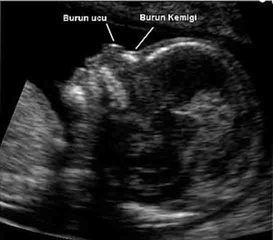

Down Sendromu Nedir?Down sendromu, bireylerin 21. kromozomunun trisomi (üçlü) durumuyla karakterize edilen genetik bir durumdur. Bu durum, genellikle fiziksel gelişim, bilişsel işlev ve belirli sağlık sorunları üzerinde etkili olabilir. Down sendromlu bireylerin belirli fiziksel özellikleri ve gelişimsel gecikmeleri olabilmektedir. Down Sendromunun BelirtileriDown sendromunun belirtileri, bireyler arasında değişiklik gösterebilir, ancak genel olarak aşağıdaki özellikler gözlemlenir:

SonuçDown sendromu, bireylerin yaşamını etkileyen genetik bir durumdur. Belirtileri arasında fiziksel özellikler, gelişimsel gecikmeler ve sağlık sorunları yer alır. Erken tanı ve müdahale ile Down sendromlu bireylerin yaşam kalitesi artırılabilir ve potansiyelleri en üst düzeye çıkarılabilir. Eğitim, aile desteği ve uygun sağlık hizmetleri, bu bireylerin sosyal ve duygusal gelişiminde kritik bir rol oynamaktadır. Ekstra BilgilerDown sendromu hakkında daha fazla bilgi edinmek isteyen bireyler, genetik danışmanlık hizmetlerinden yararlanabilir. Ayrıca, birçok dernek ve kuruluş, Down sendromu olan bireyler ve aileleri için destek ve kaynaklar sağlamaktadır. Eğitim kurumları, Down sendromlu bireylerin ihtiyaçlarına uygun özel programlar ve destek hizmetleri sunarak, onların sosyal entegrasyonunu ve gelişimini teşvik etmektedir. |